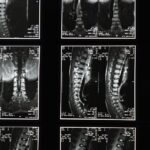

La décompression spinale est une technique non invasive qui consiste à créer de l’espace entre les vertèbres. Cela permet de réduire la pression sur les disques et les nerfs de la colonne vertébrale. Grâce à un appareil spécialisé, une traction contrôlée est appliquée, offrant un soulagement significatif pour les douleurs au dos, notamment celles causées par des hernies discales ou des problèmes de colonne.

La décompression spinale est une technique thérapeutique non invasive qui cible spécifiquement les problèmes de la colonne vertébrale. Elle est souvent utilisée pour traiter des conditions telles que les hernies discales, la stenose spinale et des douleurs chroniques au dos. En créant un espace entre les vertèbres, cette méthode réduit la pression sur les nerfs et les disques intervertébraux, facilitant ainsi la circulation sanguine et le processus de guérison au sein de la colonne.

La décompression spinale utilise un appareil spécialisé qui applique une traction douce et contrôlée à la colonne vertébrale. Cette traction crée un espace entre les vertèbres, permettant ainsi de diminuer la compression sur les nerfs spinalement et d’améliorer l’élasticité des disques intervertébraux. Ce processus favorise également la réhydratation des disques, permettant un meilleur fonctionnement global de la colonne vertébrale.

Les appareils de décompression spinale sont conçus pour appliquer une traction contrôlée. En allongeant doucement la colonne vertébrale, ils permettent d’augmenter l’espace intervertébral. Ce processus réduit non seulement la douleur, mais améliore également la flexibilité et la mobilité du dos. L’intégration de cette méthode dans un plan de traitement global, souvent combinée à d’autres techniques de soin comme l’ostéopathie, peut mener à des résultats significatifs pour les patients.